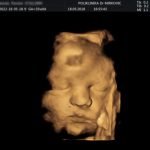

Foto: Ultrazvučni pregled trudnice

Veoma je važno pomenuti da se za 3D i 4D ultrazvuk koristi ista tehnologija. Razlika između ovih pregleda je u tome što se sa 3D ultrazvukom dobija trodimenzionalna statična slika, dok sa 4D ekspertnim ultrazvukom dobija živopisnija trodimenzionalna slika ali sa kretanjem bebe, odnosno video zapis ili trodimenzionalni film. Danas je takve zapise moguće “prebaciti” u formu fotografije (crno bele ili u boji) ili snimiti na USB prenosivoj memoriji, te ih sačuvati zauvek.

Foto: 4D ultrazvuk power by Poliklinika Mirković

Najpogodniji termin za savršenu sliku bebe za 3D ultrazvuk je u 27. nedelji trudnoće.